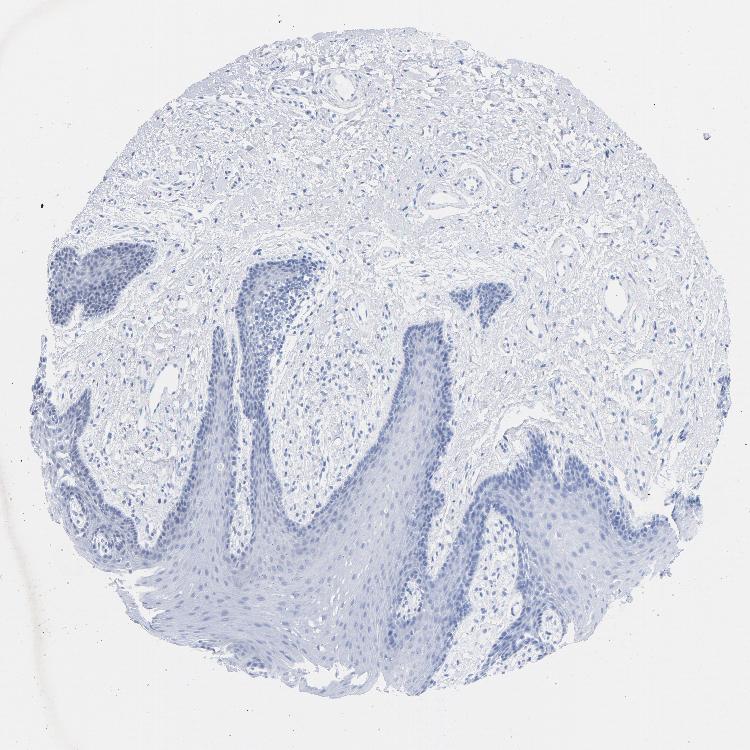

TISSUE PRIMARY DATA ORAL MUCOSA Show tissue menu

ORAL MUCOSA - Antibody stainingi

Antibody staining in the annotated cell types in the current human tissue is reported as not detected, low, medium, or high, based on conventional immunohistochemistry profiling in selected tissues. This score is based on the combination of the staining intensity and fraction of stained cells.

Each image is clickable and will lead to virtual microscopy that enables deeper exploration of all samples and also displays staining intensity scores, fraction scores and subcellular localization as well as patient and tissue information for each sample.

Antibody HPA052625Antibody CAB004300Antibody CAB004674

Squamous epithelial cells HighNot detectedLow